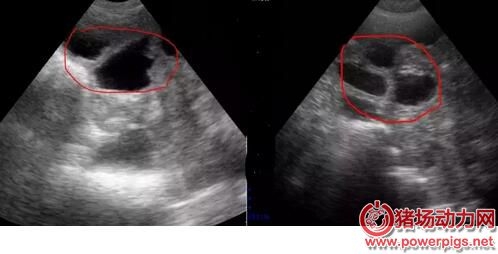

配完種之后要做的事情是什么? 肯定是檢查母豬是否妊娠啦..... 那么問題來了,到底什么時候檢查妊娠最為合適? 按理來說,早檢查可以盡快把沒有懷孕的母豬查找出來,而晚檢查可以盡可能把早期胚胎死亡的母豬也查找出來。 其實最好的策略是從輸精后第18天開始就用公豬來檢查母豬是否返情。隨后從第21天開始,第三周、第四周連續做兩次妊娠掃描診斷。 應該也有不少吃瓜群眾挺好奇不同階段的懷孕情況是怎樣的? 不同階段B超結果 第18-21天 在豬受孕18天后,B超已經可以檢測到胚泡,但是由于此時的胚泡形態較小,檢測時不容易被發現,需要操作員消耗大量時間來尋找。 母豬早期孕檢技巧: 1.母豬配種后18-21天; 2.測定時先找到膀胱暗區,小角度緩慢變換探頭探掃方向,在膀胱暗區前上方“亮帶”以上細致查找疑似的黑洞。 第21-35天 22-25天的胚胎很容易發現,此時將探頭放在檢測“三角區中”,只要位置正確立刻能發現孕囊,此時孕囊主要顯示為一個個的“黑洞”。 測孕小技巧 1.18-25天期間胎囊極速增長 2.早期胎囊為圓形或橢圓形,1-2天之后多數變為不規則 第25-35天 25-35天,孕囊會放慢變大的速度,逐步從“黑洞”內可看到一些白色的亮光出現,是胎兒的超聲反射,又稱為胎體反射。 測孕小技巧 1.25天以后可見胎體反射,此后胎體占了胎囊的大部分 2.32天時,能顯示胎兒骨骼鈣化的強回聲 第35-65天 35-65天,孕囊和胎兒會一起長大,會更容易發現“黑洞”中有亮斑,系胎兒的超聲反射,也稱胎體反射,此時的圖形孕囊和胎體反射會比25-35天期間更大,更明顯。“黑洞”面積減少,是因為羊水減少。 測孕小技巧 1.35天時,呈現胎兒骨骼鈣化的強烈回聲,羊水面積減少 2.45天時,胎兒體腔分化 第65-100天 65-110天,胎兒已經長大,羊水減少。80天,胎兒的肋骨可清晰見到,從不同角度可呈現“虛線橢圓”亮斑,或者“弧形”亮斑。 測孕小技巧 1.80天時,胎兒脊柱清晰顯示 2.95天時,胎兒脊椎、胸骨及體腔分辨清晰 不過也有些小伙伴反映,母豬經常返情,到底是什么原因呢?妊娠成功又需要些什么條件呢? 發情周期約21天。在授精后18-24天發情的母豬(沒有懷孕)稱為規律性返情母豬。以此類推,在42天或者63天左右返情的母豬也稱為規律性返情母豬,返情高峰期分布在這些天。分散在其他天數的稱為非規律性返情母豬。 返情 返情/復配的原因 最常見的原因——授精管理差;催情不足;發情不充分/太短;授精時間選擇好;3周后返情;發情檢查不足;授精時間選擇不好;“發情周期”小于18天;3周和/或6周后返情 配種員:態度,工作壓力 管理系統:催情/發情檢查、輸精管理、數據記錄 營養:喂料量和飼養管理 欄舍:飼養密度、環境、光照、溫度、占用率 母豬:出生缺陷,發育狀況 繁殖與傳染病 種豬場,疾病很少成為繁殖問題的一個重要因素,傳染病通過以下兩套途徑殺死胚胎: 傳染病病毒損壞了胚胎、胎膜或者子宮,引起胚胎死于子宮中(如細小病毒、藍耳病毒); 發燒引起前列腺素的大量釋放,前列腺素會引起流產(如豬丹毒、流感、腸道病毒、經典豬瘟、肺或腸道傳染病引起的發燒)。因此在發燒期間要用退燒藥。如果多個母豬幾乎同時流產的話,要考慮傳染病可能是問題的源頭。 寄生蟲:由疥螨、豬虱或者皮膚狀況不好引起的皮炎會使母豬焦躁不安。這種焦躁不安也是造成母豬返情的一個原因。 如果懷疑是疾病問題(不吃料、精神萎靡、皮膚發白、糞便),一定要測量母豬的體溫。涂點潤滑劑或者唾液,將溫度計插入母豬肛門內至少5cm。讓溫度計的頂端緊貼著腸壁,糞便或者腸道內的空氣都會影響測定結果。健康妊娠母豬的體溫是38-39°C,超過39.5°C就是發燒了。 氣溫 熱應激會導致母豬流產、返情。 夏天,不要在一天中最熱的時候喂豬;在豬舍向陽面,用塑料薄膜、石灰或者乳化漆遮蔽窗戶;提供平和、安靜的環境;高溫時不搞預防接種;每天檢查配種舍、待配舍和妊娠舍的溫度。 9月中旬到10月底,會出現秋季繁殖力下降現象:后備母豬發情開始變慢,非規律性返情和規律性返情或流產越來越多。 秋天晝夜溫差最大,為預防秋季繁殖力下降,從7月底開始將光照時間增加到每天16個小時,同時要確保配種舍和待配舍晚上的溫度不要太低(<18°C),提前做好通風管理,避免出現賊風。提高斷奶后的和配種后的母豬的飼喂量。因為低溫條件下,更多的能量用于維持需要,從而使得用于繁殖的能量減少。 分析 少于18天的發情期從生理學角度上講是不可能的。 3周左右的規律性返情的責任在于配種員,此外妊娠早期會有胚胎死亡。對于36-48天或者56-68天出現的返情,3周時出現的返情被錯過的可能性極大。 25-36天非規律性返情的原因常常是胚胎死亡。在此期間未被發現的母豬過21天會再返情,即在49-56天返情。 妊娠成功的因素有哪些 配種員:催情、發情檢查、輸精時間、輸精技術 公豬:精液質量、精液儲存、精液貨架壽命、公豬差 母豬/胚胎:母豬體況不好、應激、疾病、光照(強度和時間) 再者,又有大伙們表示母豬流產也不少見,求解求解? 胚胎死亡發生的階段 排卵:卵子少或質量低(營養不良); 受精:授精不佳,原因:配種員或公豬; 胚胎死亡:胚胎可能死于各種原因,如疼痛或瘸、轉運應激、喂料站工作不正常、疥螨、為爭奪統治地位而打斗、環境不良、能量負平衡; 胎兒死亡(妊娠35天以后):子宮內空間不足(胎兒太多)或者死于發燒/疾病(不常見)。 胚胎存活的關鍵 在妊娠35天之前保持平和、安靜是必不可少的,因為此前胚胎對子宮內環境變化還非常敏感。從妊娠后第12天到第18天,胚胎發出雌激素信號,所以黃體完整保留,妊娠繼續。骨骼的形成于妊娠后第30天。 來源:溫氏養豬公開課 |